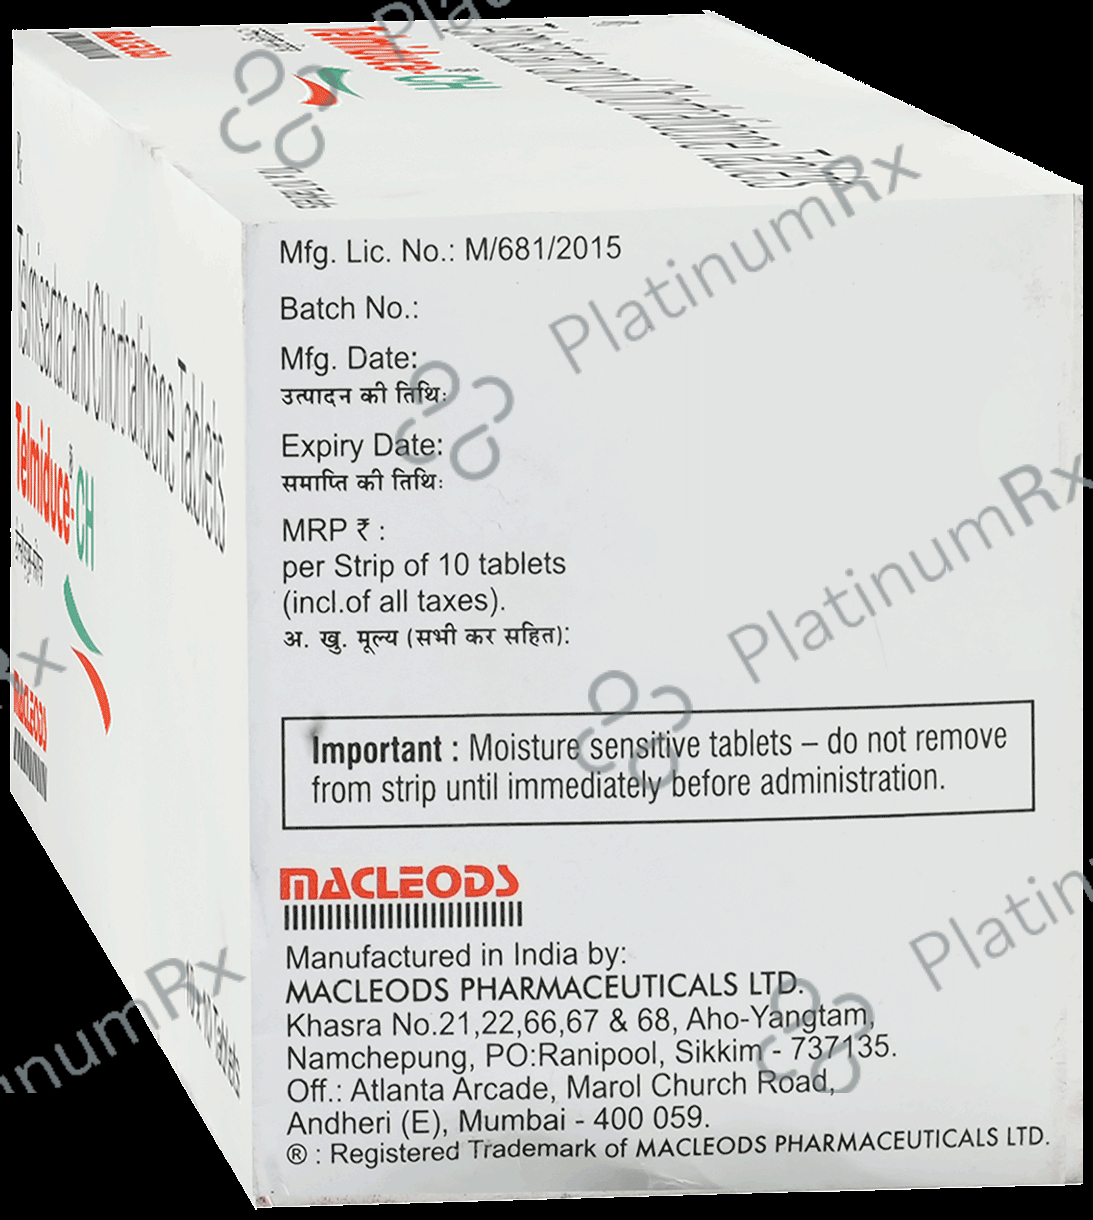

Telmiduce CH 40mg/12.5mg Tablet

Macleods Pharmaceuticals Pvt Ltd

Telmiduce CH 40mg/12.5mg Tablet

Macleods Pharmaceuticals Pvt Ltd